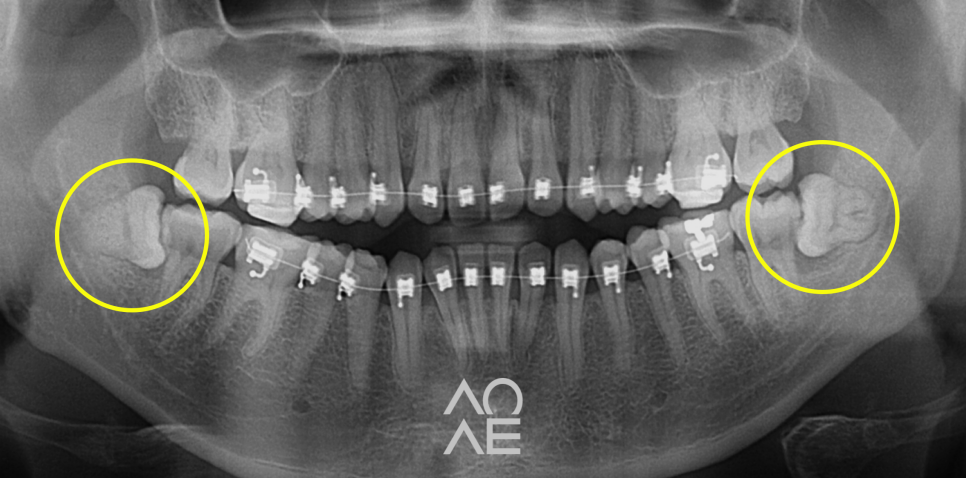

위 주소로 내원하신 학생분이신데요

저희 치과에서 교정을 하고 계셔서

사랑니의 존재는 익히 알고 있었는데요

그럼에도 사랑니는 대학병원에 가야하는지

고민하시면서 말씀을 해주시더라고요.

파노라마라고 불리는 X-ray 를 보니

걱정하신 것 만큼 심각한 상황도 아니라서

당일 발치를 진행하였습니다

24.6.29

5분만에 발치하였습니다!

| 발치 전 | 발치 후 |